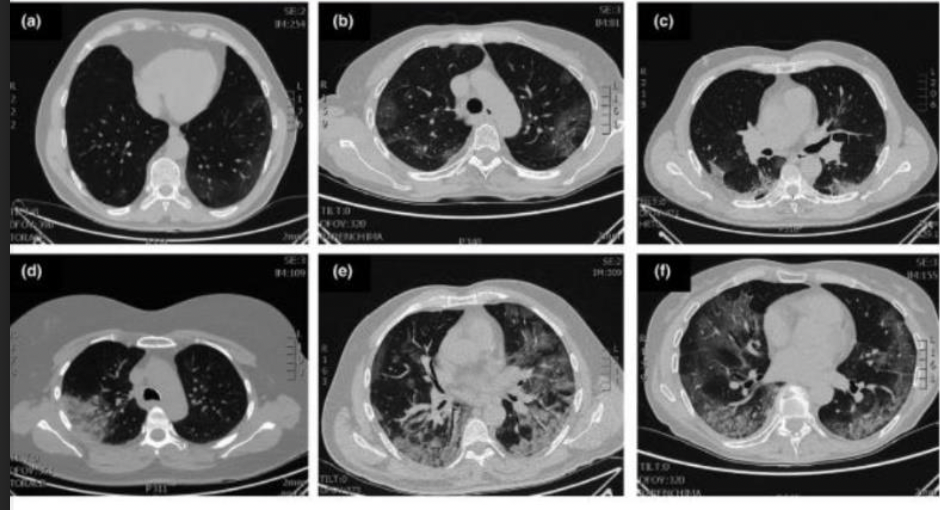

COVID 19 איך נראית פגיעה ריאתית לאחר?

ground glass opacity בשתי הריאות

לעיתים יש קונסולידציה רצינית

טיפול:

סימפטומים קלים- בבית

מצב בינוני- אשפוז, נוגדנים מונוקלונלים

קשה- טכיפניאה מעל 30 לדקה, סטורציה מתחת ל93, הסכנה העיקרית היא התגובה החיסונית- צריך לטפל בציטוקינים עי סטרואידים.

remdesivir- מונעת רפליקציה של הוירוס.

תסמונת פוסט קוביד- הנזקים הריאתיים יכולים להשאיר נכות חמורה אצל המחלימים כמו שינויים אינטרסטיציאליים.